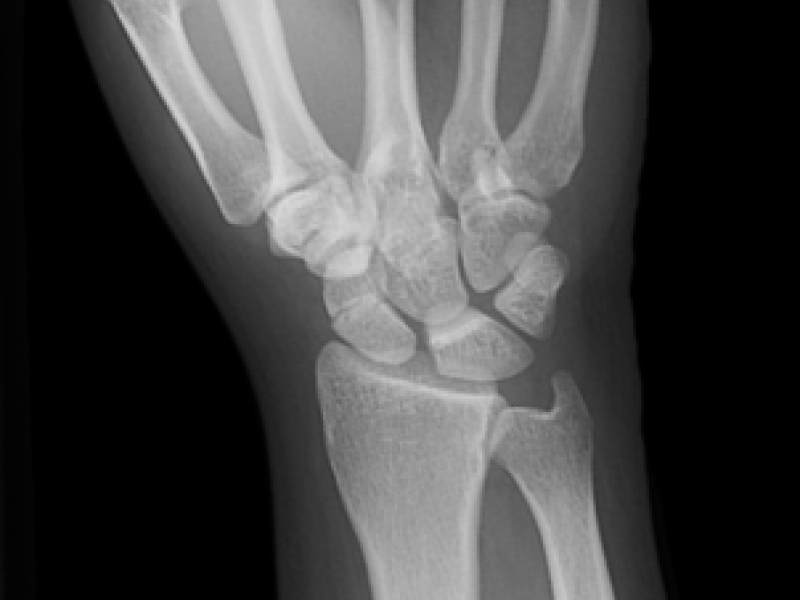

25 year-old female presents following a fall from her horse